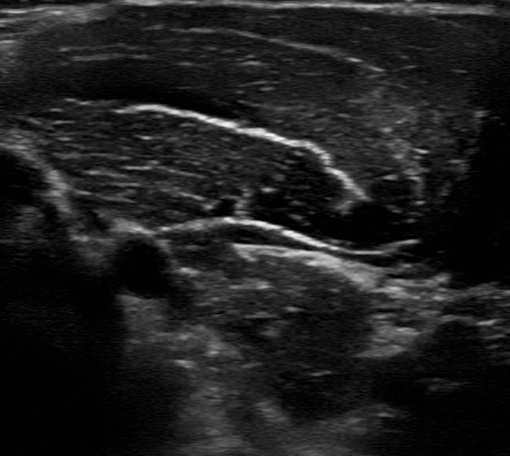

膝痛への超音波エコーガイド下鍼

膝周囲の筋肉・靱帯・神経の状態を確認しながら施術。原因を見極め、歩行時の痛みや違和感を改善へ導きます。